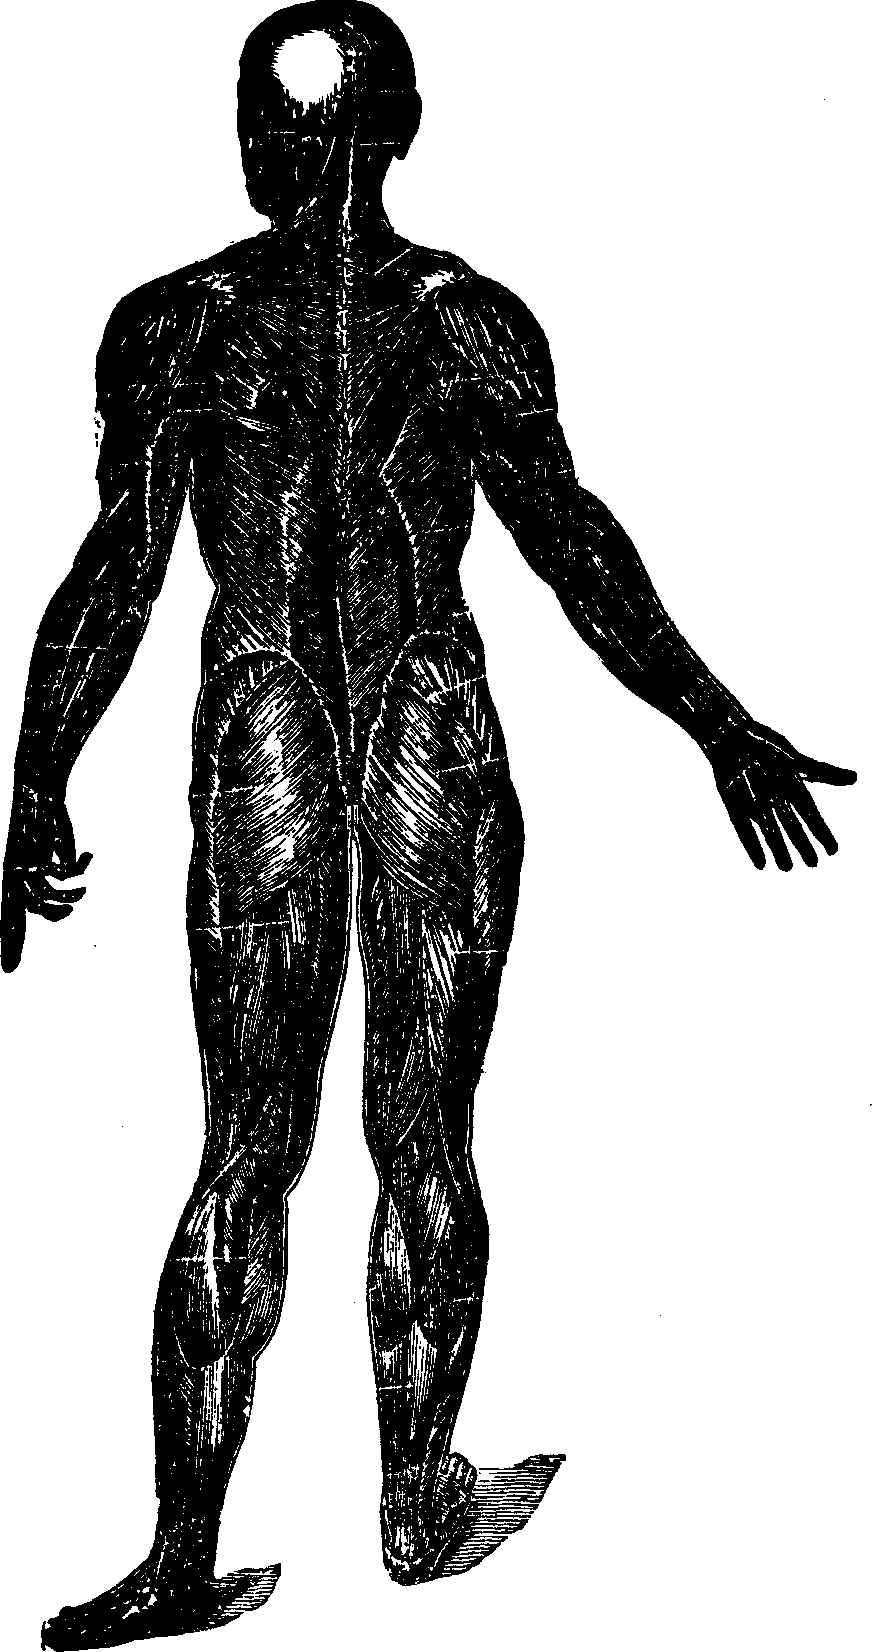

Fig.

25. A representation of the superficial layer of muscles on the posterior

portion of the body.